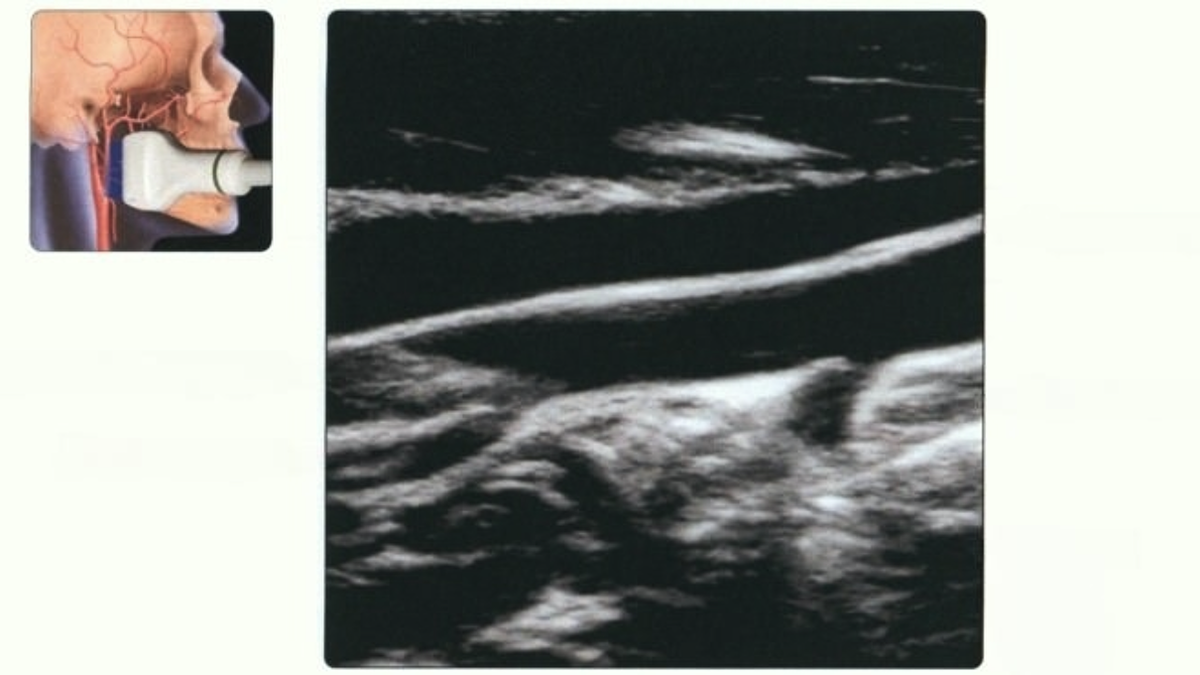

Светлана Владимировна до сих пор помнит, как сидела в кабинете кардиолога, глядя на монитор УЗИ. Врач водил датчиком по шее, молчал, потом вздохнул: — Бляшки подросли. Холестерин у вас как? — Да я же... — у Светланы перехватило горло. — Я же всё делаю! Сало последний раз ела на юбилее сестры, это года четыре назад было. Масло сливочное даже не покупаю. Яйца? Ну, белки иногда. Творог — нулёвка. Что ещё нужно-то?! А бляшки себе растут. Медленно, но верно. Светлана не одинока — знаете, сколько таких историй? Люди отказываются от всего жирного, пьют статины горстями, холестерин падает до приличных цифр... а сосуды всё равно зарастают. Почему? Когда делаешь всё правильно — а толку ноль Сколько лет нас этим пугали? Холестерин — главный злодей. Бляшки — это он, родимый, налипает на стенки сосудов. Меньше жира в рот положишь — меньше и осядет. Вот и Светлана Владимировна поверила. Таблетки пила по часам. Майонез выбросила. Курицу варила без кожи, хотя раньше обожала хрустящую корочку. Анализы

Светлана Владимировна до сих пор помнит, как сидела в кабинете кардиолога, глядя на монитор УЗИ. Врач водил датчиком по шее, молчал, потом вздохнул: